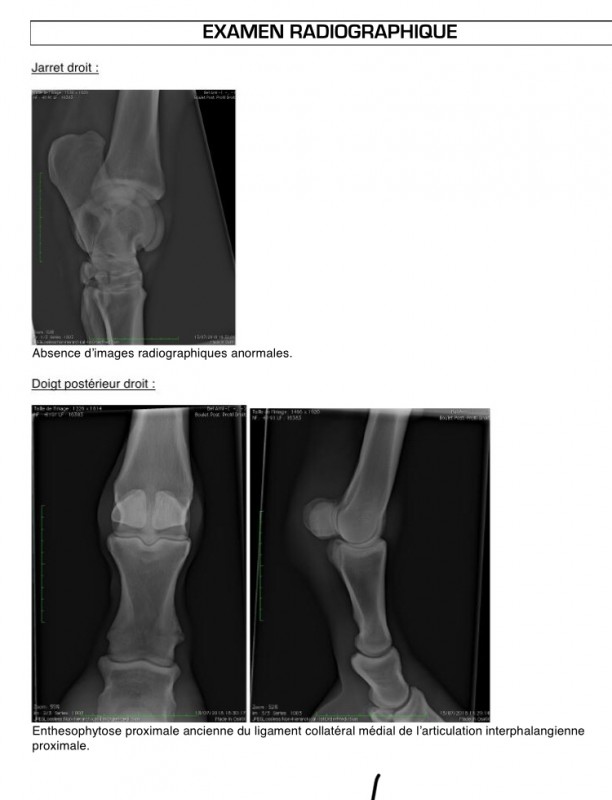

J'ai fait une échographie par vois anal voilà les résultats

On va ensuite faire une échographie du postérieur pour voir les suspenseur.

J'ai mis les résultats de l'écho et de l'examen dans le commentaire au dessus